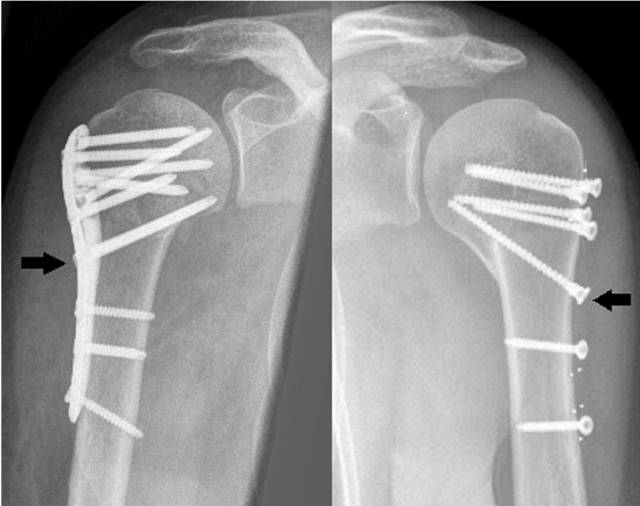

图1.

肱骨近端骨折锁定钢板固定时,内侧支撑螺钉(黑色箭头)维持肱骨内侧柱稳定性。